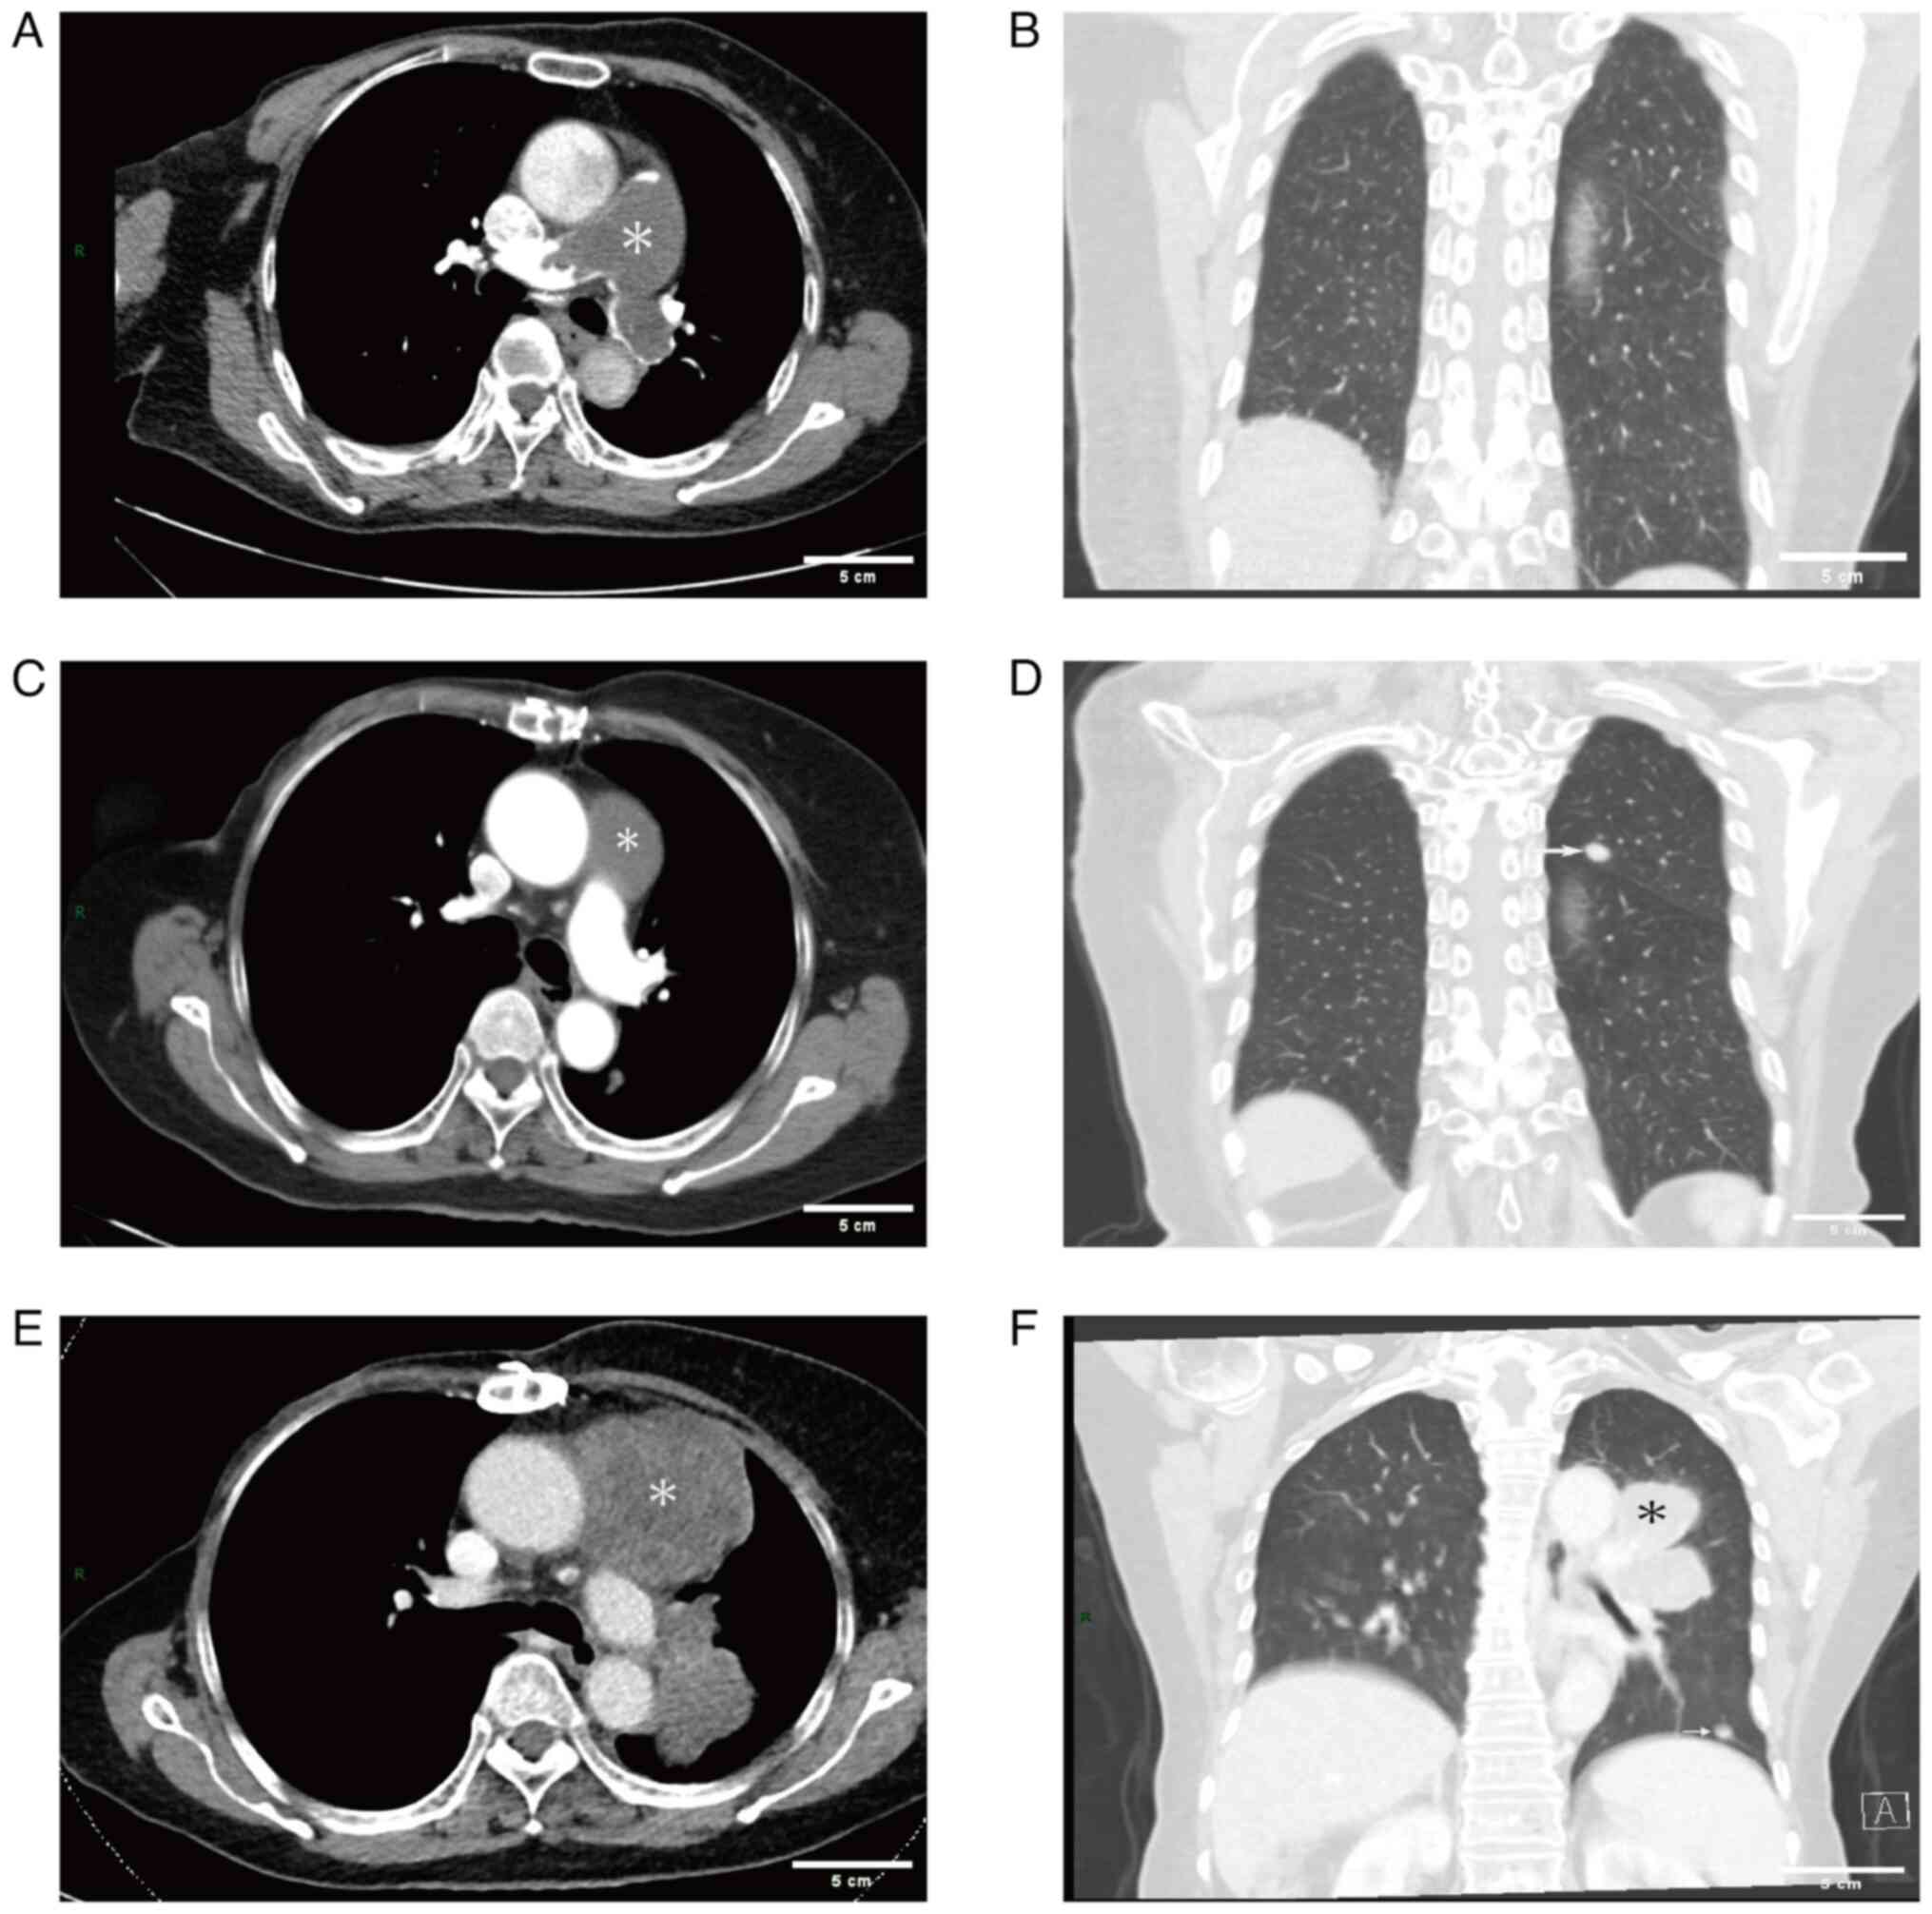

Figure 2.

Chest imaging results. (A) Preoperative CTPA showed dilation of the pulmonary trunk (~37 mm), filling defects in the main pulmonary artery, as well as the left and right pulmonary arteries, (B) with no nodules in the lung. (C) Chest-enhanced CT in December 2020 showed a low-density filling defect in the main pulmonary artery and (D) a 10-mm nodule in the upper left lobe of the lung. (E) Repeat chest-enhanced CT in March 2021 showed a significant enlargement of the low-density lesions (~68×67 mm) in the main pulmonary artery, (F) as well as multiple fresh soft-tissue masses in the left lung. Asterisks indicate the location of the lesion. Arrows point to the lung nodule. CTPA, computed tomography pulmonary angiography.

Following surgery, the patient experienced a satisfactory recovery with notable improvement in clinical symptoms. A postoperative TTE revealed no abnormal mass in the pulmonary artery and a marked decrease in pulmonary artery pressure (34 mmHg) compared with preoperative levels (Fig. 1E and F). Despite the recommendation for a positron emission tomography-CT (PET-CT) scan, the patient declined and was discharged in May 2020. Subsequently, the patient opted to undergo treatment with oral anlotinib (12 mg on days 1–14) according to the 2019 Chinese Society of Clinical Oncology treatment guidelines for soft-tissue sarcoma (8) and due to the demonstrated significant efficacy of anlotinib in treating soft-tissue sarcoma in multiple clinical trials (9). In December 2020, the patient reported chest tightness, dyspnea and chest/back pain. An enhanced CT scan of the chest performed on 3 days later revealed a low-density filling defect in the main pulmonary artery along with a 10-mm nodule in the left upper lobe initially suspected to be metastatic lesions (Fig. 2C and D). The patient opted to continue oral anlotinib treatment while remaining hesitant to modify the treatment regimen. A subsequent enhanced CT scan of chest and abdomen performed in March 2021 showed substantial enlargement of the low-density lesions within the main pulmonary artery (~68×67 mm), as well as multiple fresh soft-tissue masses in the left lung; however, no abnormalities were observed within the abdominal region (Fig. 2E and F). Concurrently, the levels of tumor marker CA125 were increased to 66.9 U/ml (reference value, 0–35 U/ml) and exhibited a progressive upward trend as the disease progressed. By April 2021, the level of this marker had peaked at 267 U/ml.